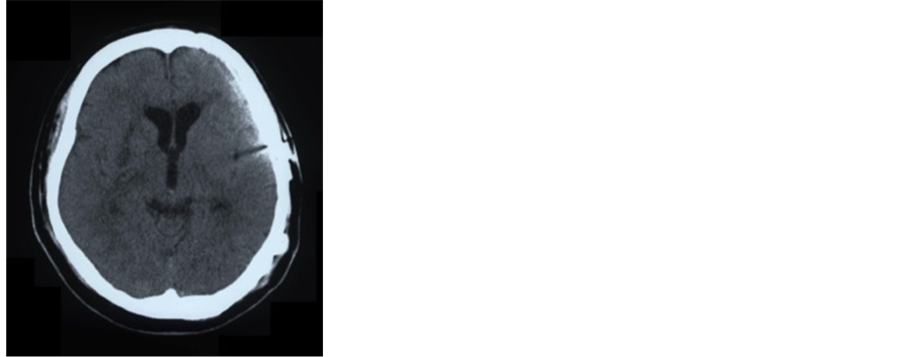

About 25 months after SAH, he was admitted to our hospital for cranioplasty using a custom-made hydroxyapatite (HAP) ceramic implant. On admission, he was clinically obese (body mass index: 34.9) and he had a past history of hypertension and smoking until the onset of SAH. On physical examination and CT scan, a depressed area was located on the temporal part of the skull, but he had no neurological findings (Figure 2). We performed cranial reconstruction surgery using a custom-made HAP ceramic implant (Figure 3). No intraoperative fabrication was needed, and there were no tenting sutures to the reconstructed dura mater. No intraoperative complications, such as injury to the dura, occurred. On the day after the operation, a putaminal hemorrhage was on the opposite side on CT scan (Figure 4). However, there were no physical or neurological findings. Compared to preoperative findings, depression of brain substance in the left frontal lobe and temporal lobe had improved, and the frontal horn of the lateral ventricle was slightly deviated to the left. No adverse events occurred in the postoperative course, and he was discharged from the hospital two weeks after surgery. Follow-up CT scan performed 20 days after surgery showed that the intracerebral hematoma was completely absorbed and the deviation of the frontal horn of the lateral ventricle was improved (Figure 5). Six months after cranioplasty, his skull retained a good shape (Figure 6), and he is keeping in a good course for more than two years postoperatively with no subsequent issues.

Figure 5. CT scan performed 20 days after surgery showed no intracerebral hematoma and no deviation of the frontal horn of the lateral ventricle.